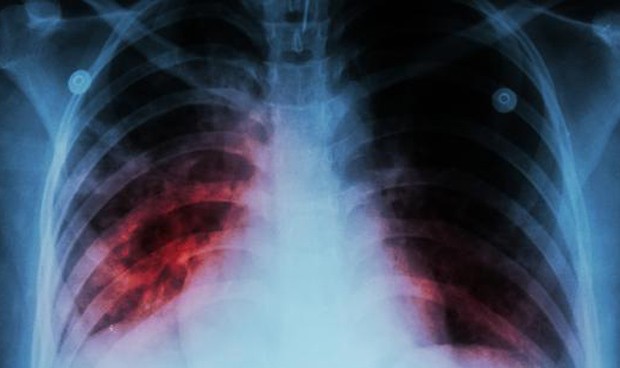

El Departamento de Salud del Gobierno Vasco y Osakidetza han puesto en marcha el protocolo de actuación por tuberculosis tras haber detectado un caso en Vitoria. Siguiendo con dicho protocolo, se han adoptado ya las medidas preventivas establecidas y se ha iniciado el estudio de contactos en el entorno de la persona afectada.

En un comunicado, el Departamento de Salud ha recordado que la tuberculosis es una enfermedad que no se ha erradicado, pero que en la actualidad se cura con un tratamiento adecuado. Aunque aún son datos provisionales, en Euskadi el pasado año 2018 se detectaron un total de 201 casos de tuberculosis, con una tasa de 9,2 casos por 100.000 habitantes.

Salud ha precisado que es la tasa más baja registrada en la última década. En el año 1998 fueron 720 las personas con tuberculosis confirmadas, con una tasa del 34,3 por 100.000 habitantes.

La tuberculosis se contagia por vía aérea al toser o al hablar, y en general su transmisión requiere una convivencia íntima y prolongada en el tiempo.